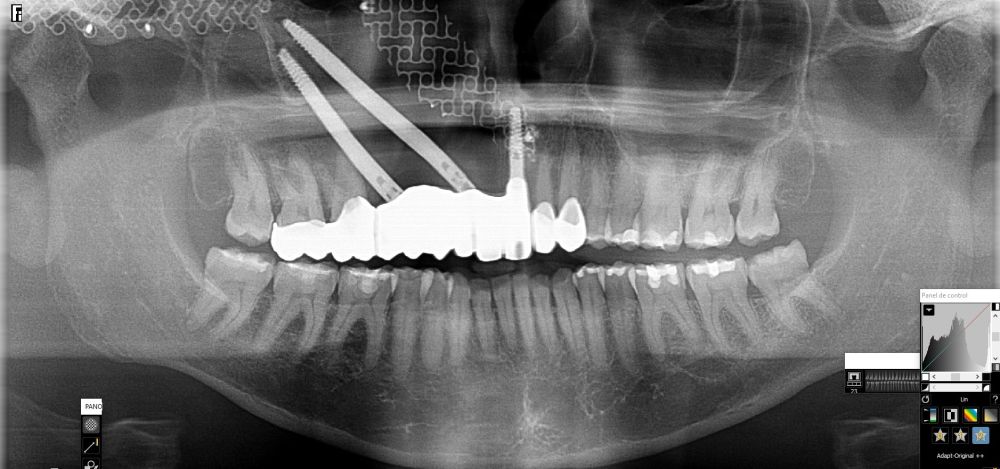

Presentamos el caso de una paciente de 47 años que acude al servicio de cirugía maxilofacial por dolor en el área sinusal derecha en Junio de 2020. Se realizó una radiografía panorámica en la que se observó una imagen sospechosa en la zona del primer cuadrante. Dichos hallazgos se confirmaron con la realización de una tomografía axial computarizada (TAC) facial y una resonancia magnética en las que se identifica una extensa lesión tumoral que ocupaba el seno maxilar derecho e infiltraba el suelo de la órbita derecha y fosa nasal derecha (Figuras 1, 2 y 3). Tras la realización de una biopsia, se confirmó la presencia de un carcinoma adenoide quístico. De este modo, se planificó la extirpación quirúrgica y la fijación mediante placas preformadas sobre un modelo impreso en poliamida (Figura 4).

Bajo anestesia general, se realizó la resección quirúrgica junto con la fijación de dos placas preformadas y colocación simultánea de dos implantes cigomáticos y un implante endoóseo en posición del 2.1 (Figuras 5 y 6). Debido a la presencia de márgenes quirúrgicos comprometidos en el informe anatomopatológico, se indicó la administración de radioterapia adyuvante. Por este motivo, se decidió realizar un puente provisional dentosoportado de 1.7 a 2.3 (Figura 7) para mejorar la situación estética y funcional de la paciente durante todo el proceso y evitar un colapso de los tejidos blandos por la radioterapia. Para ello, se tallaron los molares (1.7, 1.6) e incisivo lateral y canino (2.2, 2.3), y se fabricó un puente fresado en polimetilmetacrilato (PMMA) con refuerzo metálico (Figuras 8 y 9).

Una vez finalizada la radioterapia, la paciente se encontraba libre de enfermedad. Por lo que se procedió a la restauración definitiva implantosoportada. Tras la segunda fase, se colocaron dos pilares transepiteliales Multiunit Ò rectos y un pilar Multunit Ò angulado de 17º (Figura 10).